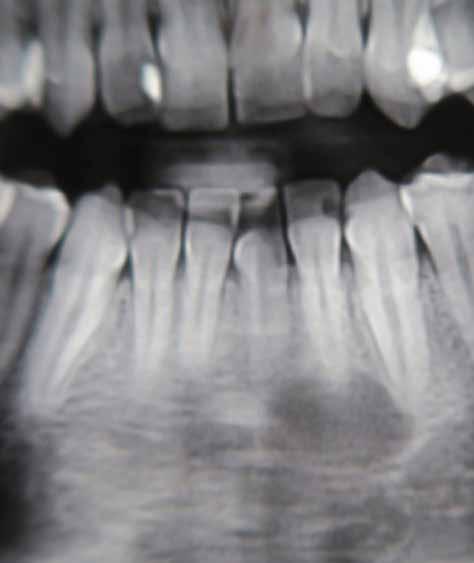

4. b ábra: A panoráma röntgenfelvétel is alátámasztja a CBCT felvételen látottakat. 4. c ábra: Az intraorális felvételen megfelelő fogpozíciók és kedvező ínyszéli lefutás ábrázolódik.

A lézerrel asszisztált felszabadítás előtt készített felvétel.

periapikális felvétel.

felvétel.

5. a ábra: 5. b ábra: A végső állapotról készült 5. c ábra: A végső állapotról készült